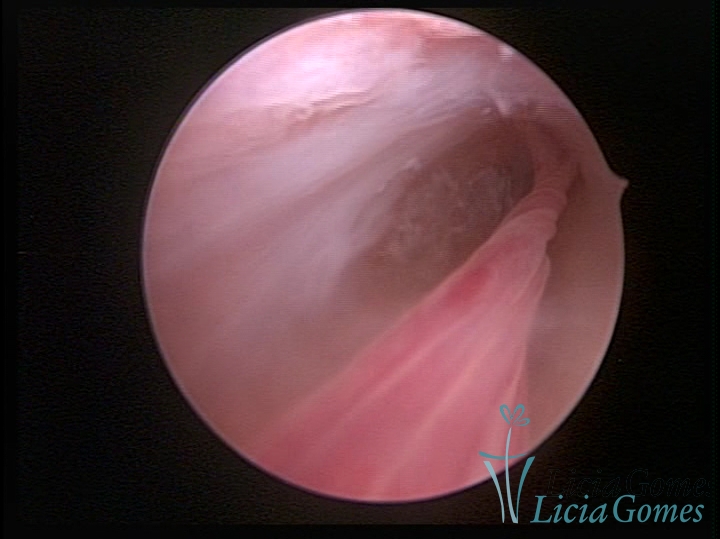

Visão panorâmica de uma cicatriz de cesárea com fio não absorvível há 30 anos